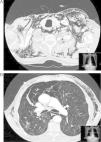

Varón de 75 años, EPOC gradoIV de GOLD, intervenido de lobectomía superior derecha por carcinoma epidermoide pulmonar. Acude al servicio de urgencias por agudización de su EPOC y es ingresado, evolucionando favorablemente las primeras 72h. El cuarto día de ingreso, tras realizar esfuerzo de defecación, presenta disnea y dolor torácico pleurítico izquierdo. En la exploración se aprecia enfisema subcutáneo en la región apical del hemitórax izquierdo. La radiografía de tórax confirmó la presencia de aire a nivel del tejido subcutáneo. Fue tratado con reposo, oxigenoterapia y analgesia, pero el enfisema subcutáneo se extendió por el tórax, la cara, los párpados y el abdomen. Se solicitó una TC torácica, que mostró la presencia de NM y ESC masivo sin evidencia de neumotórax, enfisema pulmonar y ausencia posquirúrgica del lóbulo superior del pulmón izquierdo (fig. 1). Tras 48h el paciente presentó clínica de molestias torácicas, sudoración y presíncope, objetivándose en el electrocardiograma fibrilación auricular paroxística. En esta situación se decide colocar un drenaje subcutáneo derecho (fig. 2). La mejoría clínica fue casi inmediata, pudiendo ser retirado a los 5días. Transcurridos 6meses no se ha producido recidiva.